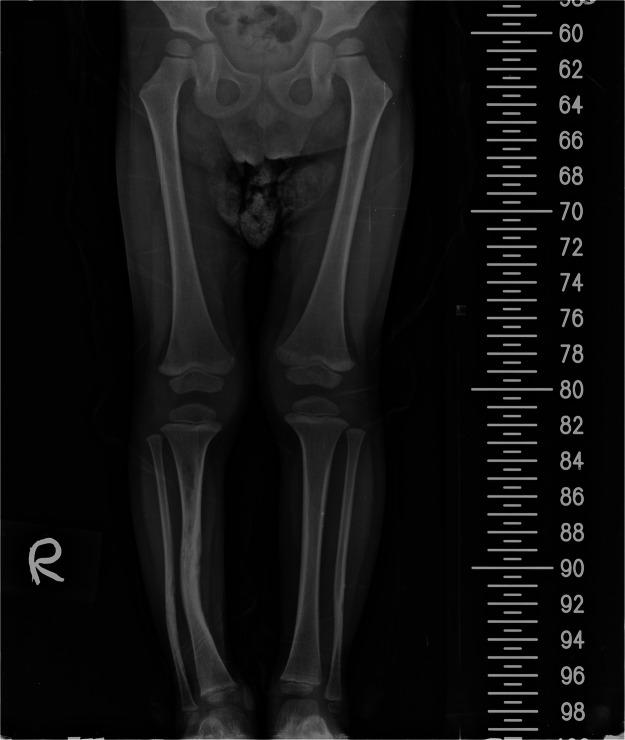

Congenital pseudoarthrosis of the tibia (CPT) is a rare pathological disease associated with neurofibromatosis type 1 (NF1). It presents with tibial bowing and can progress into a nonhealing fracture. Treatment options include conservative approaches such as serial bracing or various surgical options.Surgically, the aims are to achieve long-term bone union, prevent limb length discrepancies (LLDs), and avoid mechanical axis deviation, soft tissue lesions, nearby joint stiffness, and pathological fracture.The purpose of our study is to highlight our experience with both the conservative approach and the use of vascularized free fibula reconstruction of these deformities, including the challenges encountered with a long-term follow-up until skeletal maturity.

We present a retrospective analysis of a total of nine (9) patients consisting of three (3) girls and six (6) boys. Six (6) children were treated with a vascularized fibula flap, and the other three (3) were treated conservatively. Outcomes measured included fractures, LLD, ankle valgus deformity, donor site morbidity, and number of surgical corrections.

All patients had flap survival. Three (3) of six children had a previous failed surgery with intramedullary nail and bone graft prior to performing a vascularized free fibula reconstruction. The follow-up period ranged from 8 months to 200 months. The complications included stress fractures (50%), LLD (66.6%), and ankle valgus (33.3%). During growth phases, these children required multiple corrective surgeries.